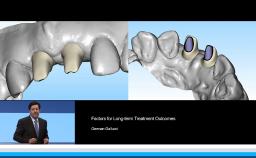

German Gallucci